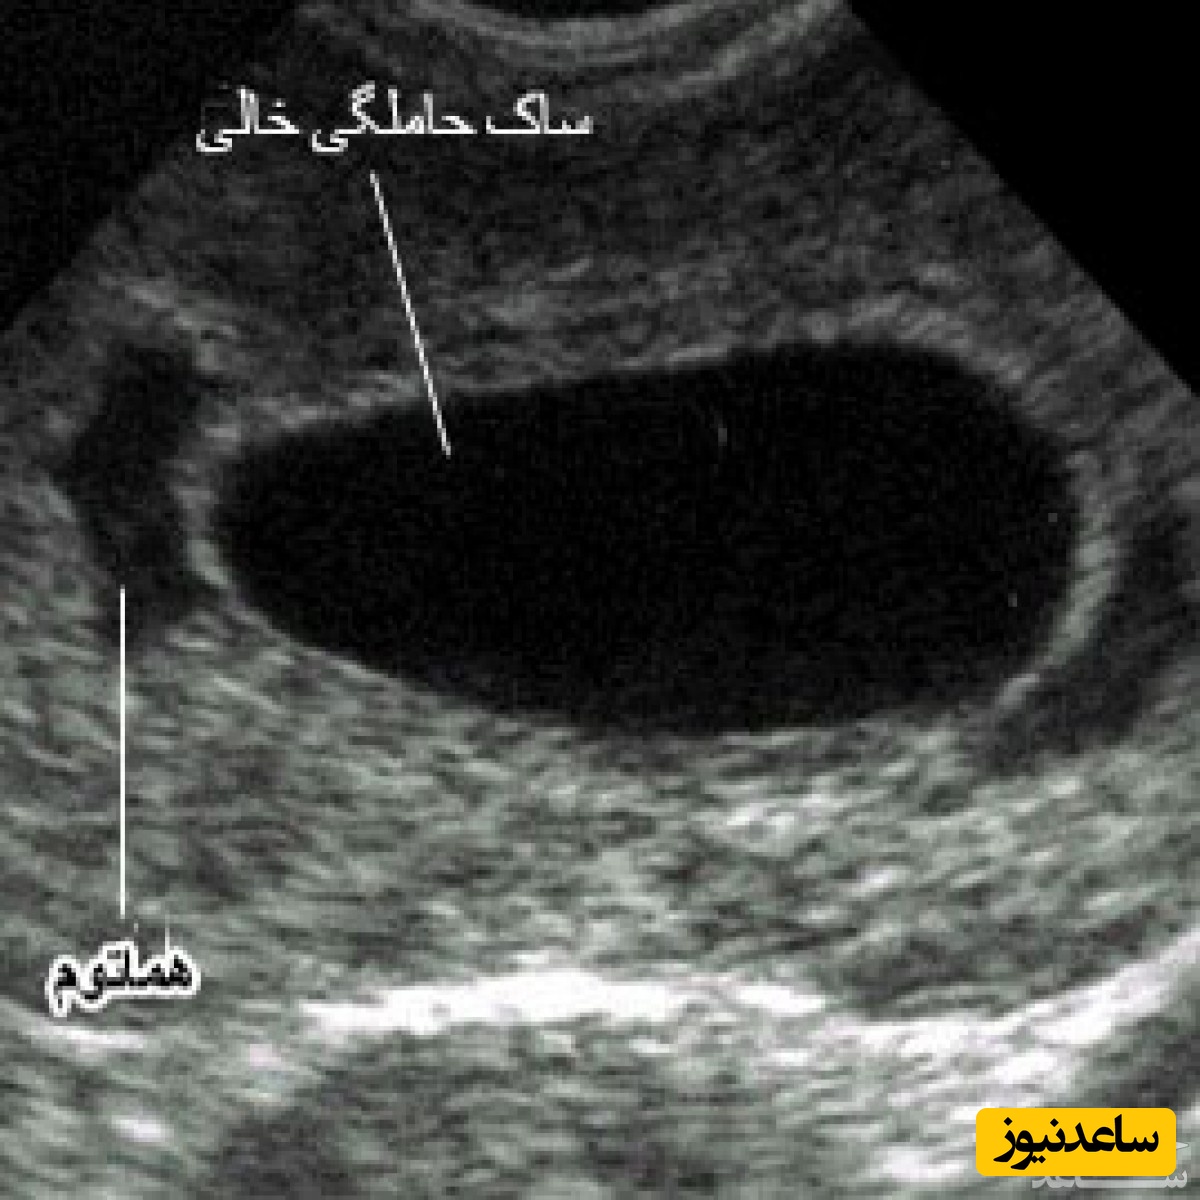

به گزارش سرویس مجله خانواده ساعدنیوز، ساک حاملگی یکی از اولین علائم بارداری است که در سونوگرافی ترانس واژینال مشاهده می شود، سونوگرافی شکمی در اوایل بارداری بسیار کمتر احتمال نشان دادن ساک را دارد. ساک حاملگی در اصل یک کیسه ای است که رویان (مرحله ی پیش از جنینی) را در بر می گیرد و حاوی مایع آمنیوتیک است. قدم بعدی در سونوگرافی مشاهده ی کیسه زرده در ساک حاملگی است. کیسه زرده به عنوان تغذیه کننده ی رویان در حال رشد عمل می کند و معمولا در سنین 5 تا 6 هفته حاملگی با سونوگرافی ترانس واژینال قابل مشاهده است.اگر در حدود هفته پنجم بارداری ساک حاملگی رویت نشود، ممکن است به دلایل مختلفی باشد.

ساک حاملگی یکی از اولین نشانه های بارداری است که می تواند در سونوگرافی واژینال و شکمی دیده شود. این ساک معمولا در سونوگرافی در هفته 5 حاملگی مشاهده می شود اما گاهی اوقات در سونوگرافی در هفته 3 حاملگی نیز قابل مشاهده است. قطر ساک حدود 2 تا 3 میلی متر است و لبه سفید و مرکزی روشن دارد.در صورتی که ساک حاملگی در سونوگرافی واژینال هفته 5 بارداری مشاهده نشود؛ ممکن است به دلایل زیر روی داده باشد.

ساک حاملگی به طور معمول در سونوگرافی واژینال بین هفته سوم تا پنجم یا هنگامی که هورمون حاملگی hcg به 1500-2000 رسیده است، دیده می شود. در صورتی که بارداری از هفته پنجم گذشته و یا سطح هورمون اشاره شده از 2000 بالاتر باشد، تشکیل نشدن ساک حاملگی و عدم دیدن آن نشان از یک مشکل است. در غیر این صورت ممکن است سونوگرافی زودتر از موعد صورت گرفته و به علت اشتباه در محاسبه زمان بارداری این مورد رخ داده باشد که باید دوباره سونوگرافی چند هفته بعد انجام گیرد.